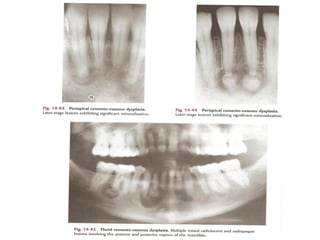

Periapical cemento-osseous dysplasia